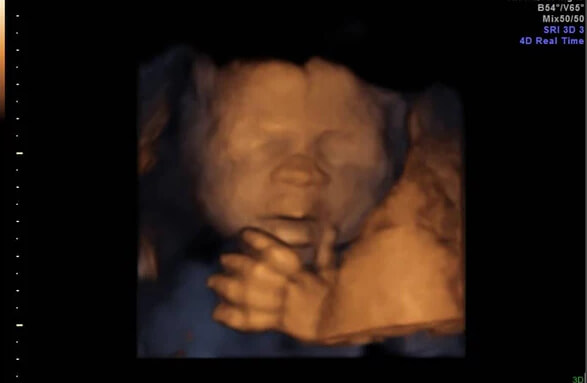

23 Haftalık Bebeğin Ultrason Görüntüsü

Öncelikle belirtmek isteriz ki bebeğinizin görüntüsü bu ultrasondaki gibi değilse endişelenmenize gerek yok; çünkü özellikle bu aylarda bebeğin çok hareketli olması 23 haftalık utrasonda farklı görüntülere neden olur:

• Bebeğiniz bu haftalarda o kadar hareketli onu ultrasonda değişik biçimlerde bulmanız ve şaşırmanız oldukça doğal!

• 23 haftalık gebelik ultrasonunda bebeğinizi gülümserken ya da dil çıkarırken bile bulabilirsiniz.

• Bebeğinizin görüntüsü size hâlâ çok zayıf geliyor olabilir; ama endişelenmeyin, bebeğinizin kilo artışı birkaç hafta içinde gözle görülür hale gelecek.

• Hamileliğin 23. haftasında bebeğin anne karnındaki duruşu ise hâlâ aynıdır; yani bacaklarını karnına çekmiş pozisyonda.